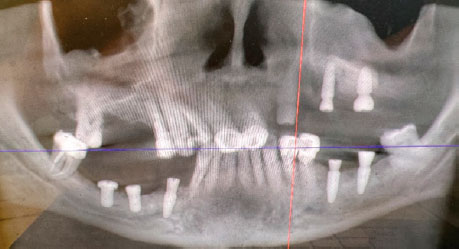

До начала стоматологического лечения выполнена компьютерная томография (КТ) зубов верхней и нижней челюсти (рис. 3).

Рис. 3. Компьютерная томограмма зубов верхней и нижней челюстей до начала стоматологического лечения

Fig. 3. Computed tomography scan of the maxillary and mandibular teeth before dental treatment